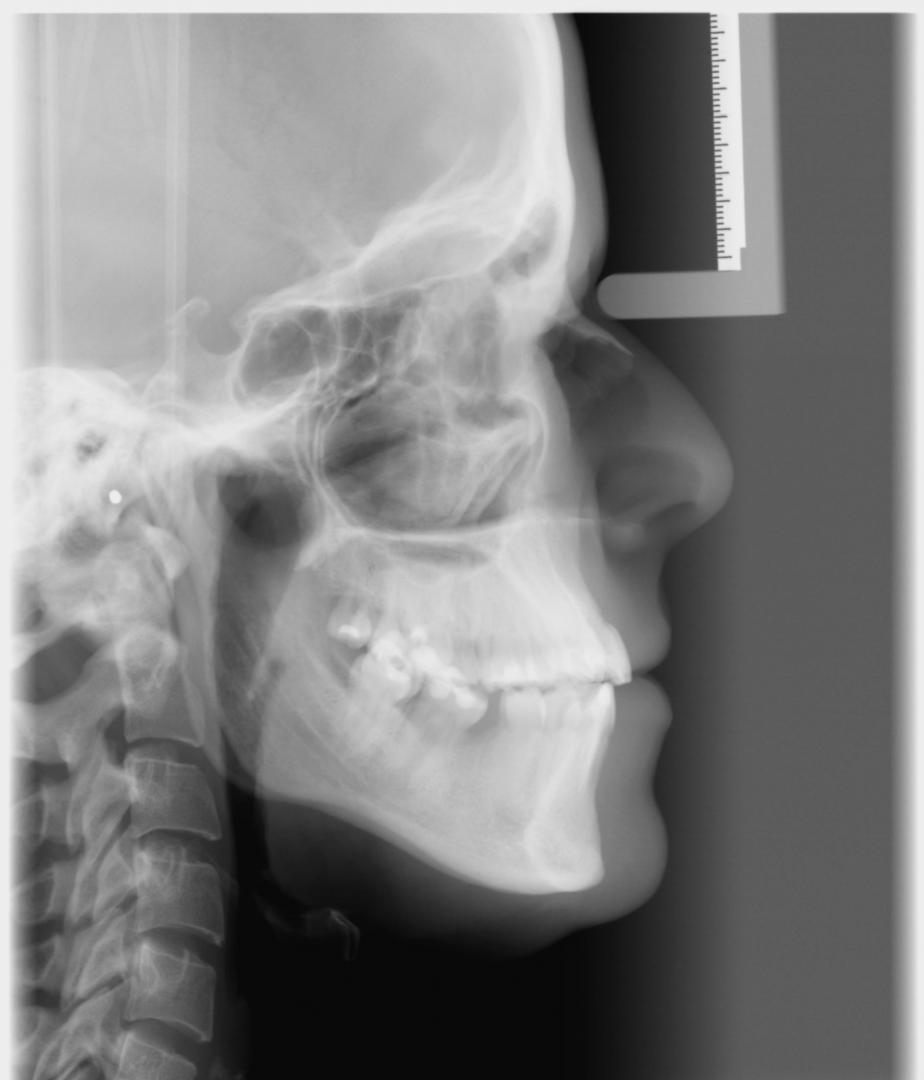

- Кефалометричне зображення